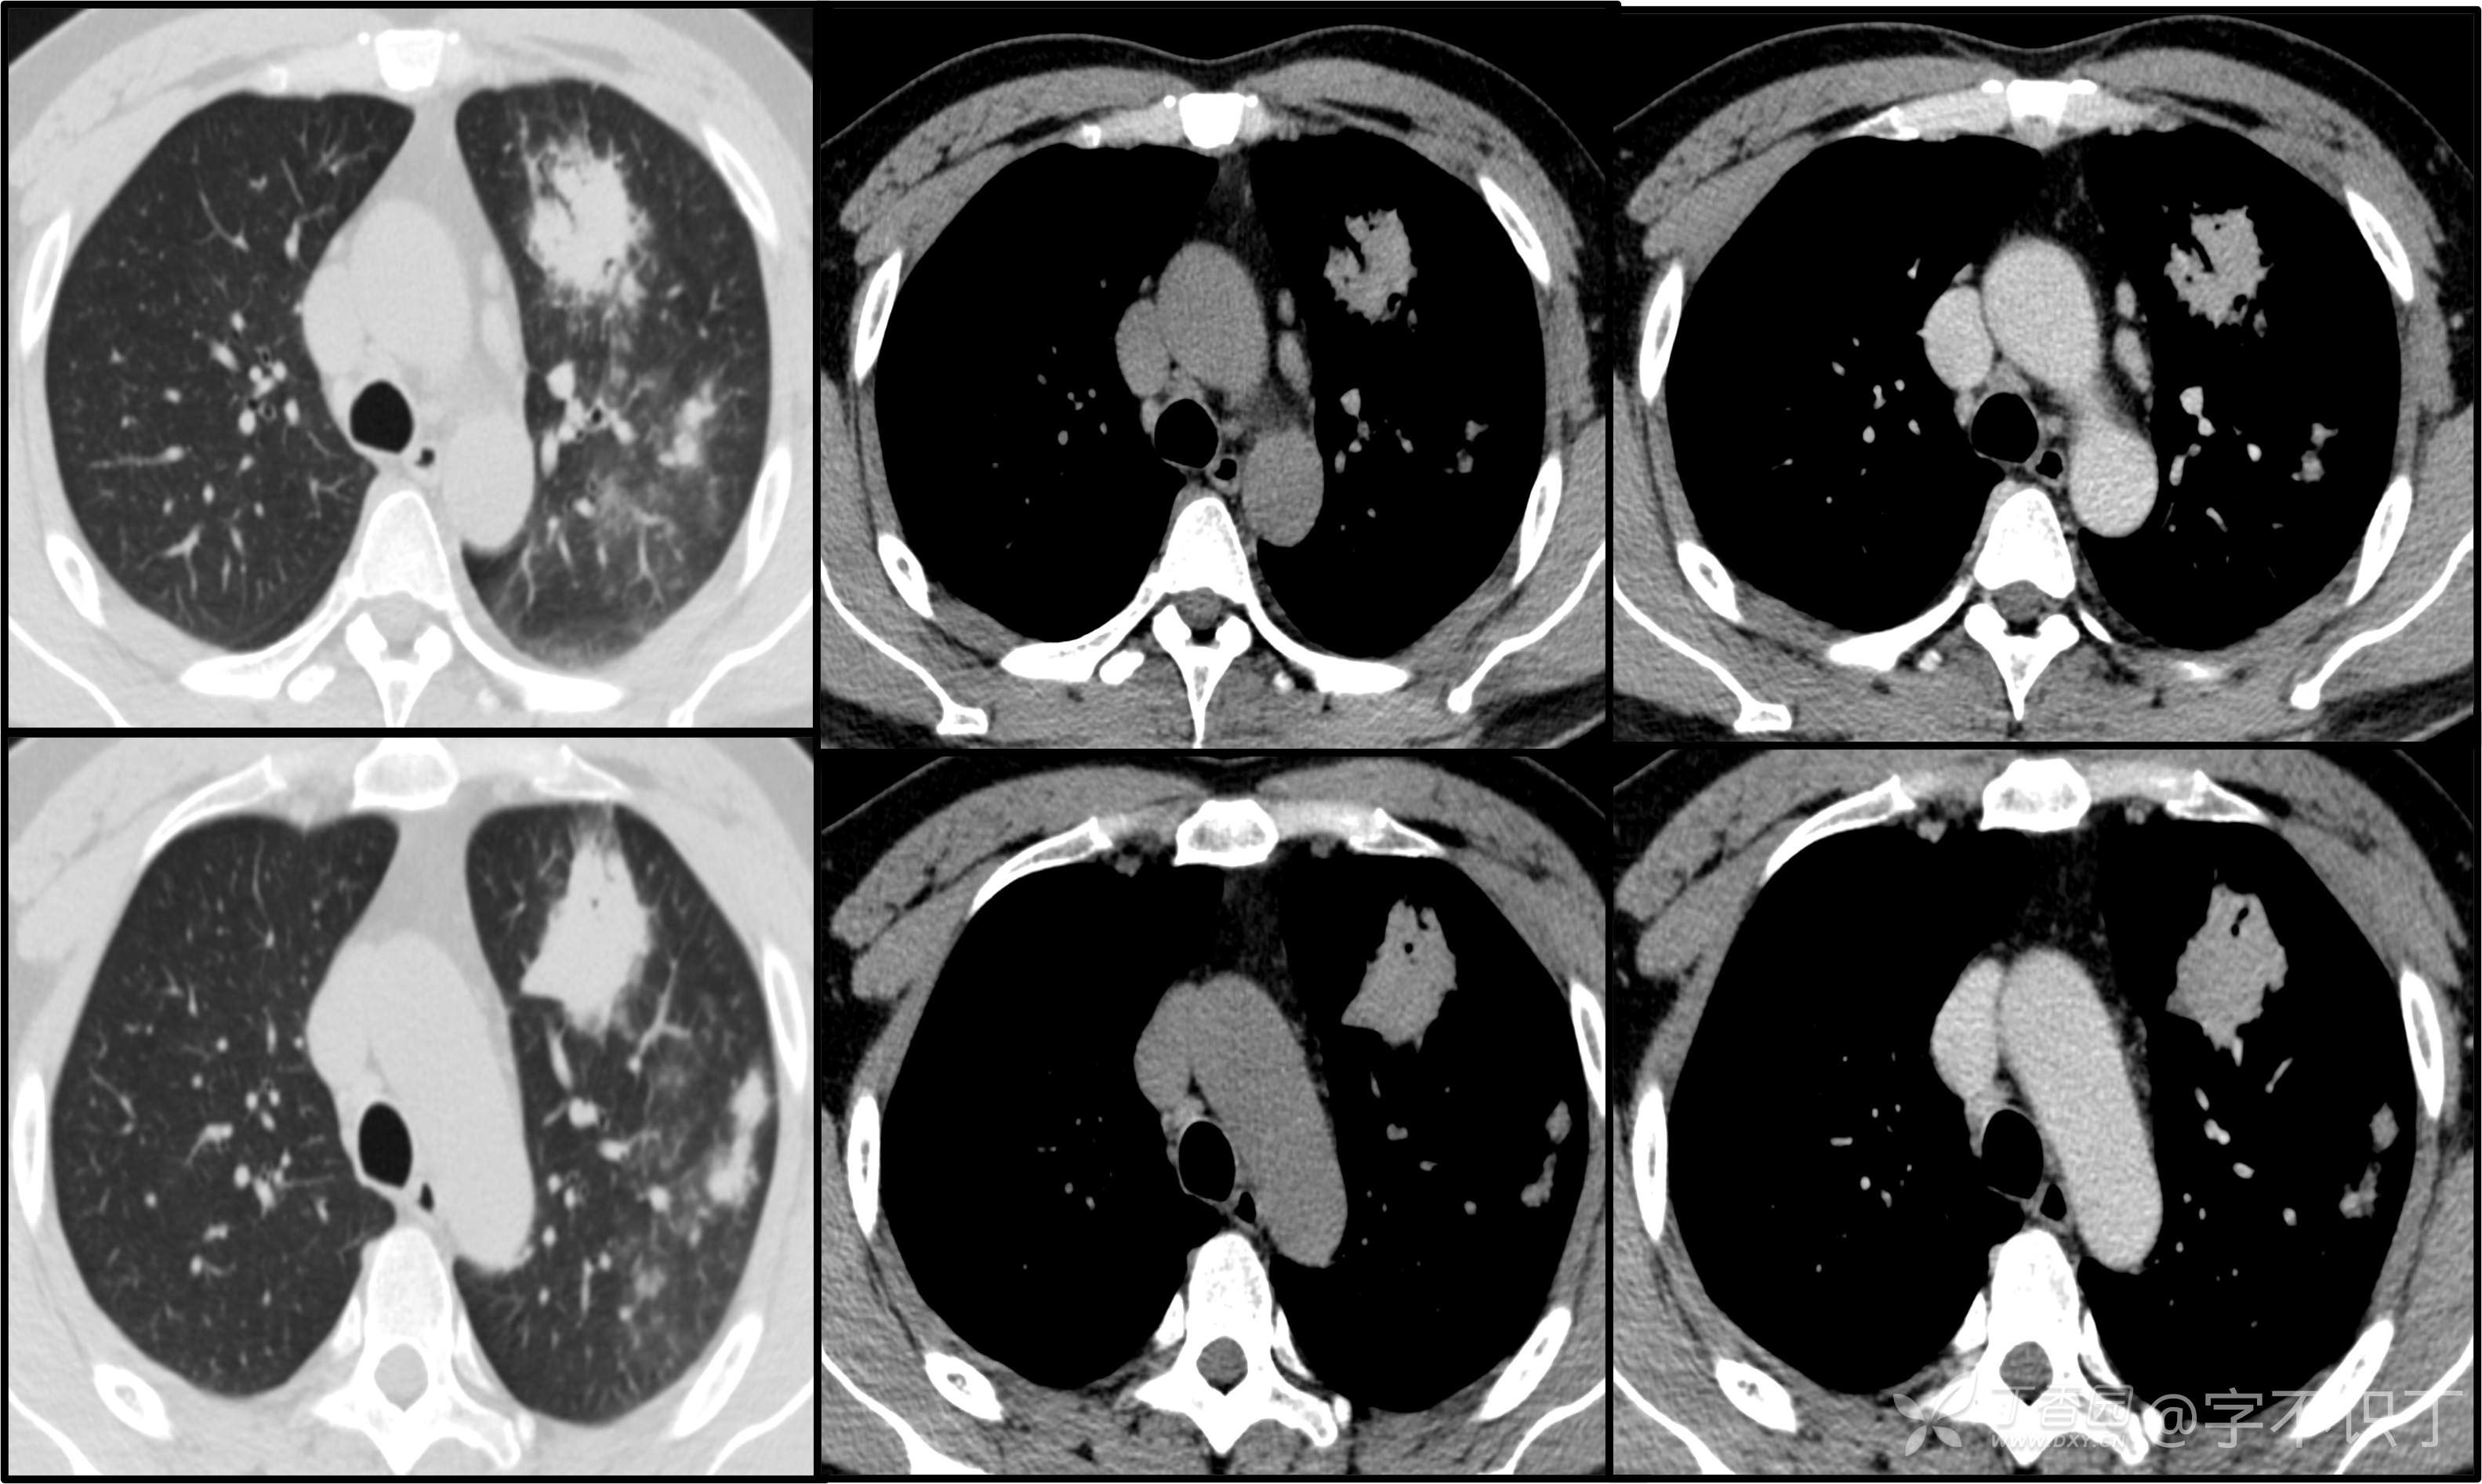

胸部病例讨论

患者性别:男

患者年龄:40岁

主诉:反复咳嗽2年,再发2月,咯血发热5天

简要病史:2年前无明显诱因出现阵发性干咳;2月前咳嗽症状较前加重,有少量白色粘液样痰,未经特殊处理,7天前咳嗽症状较前加重,伴咳黄脓样痰,痰中带血丝,予以哌拉西林舒巴坦+莫西沙星抗感染及祛痰等对症支持治疗,未觉好转,予以拉氧头孢、左氧氟沙星、布洛芬、氨溴索等对症处理,咳嗽、咳痰症状未缓解,仍有发热

体格检查:曾从事装修等工作,近半年从事煤矿管理工作。近期饮酒较频繁。既往有冶游史。

辅助检查:血液病原菌培养、分枝杆菌涂片检查、真菌涂片检查、一般细菌涂片检查、痰培养均阴性